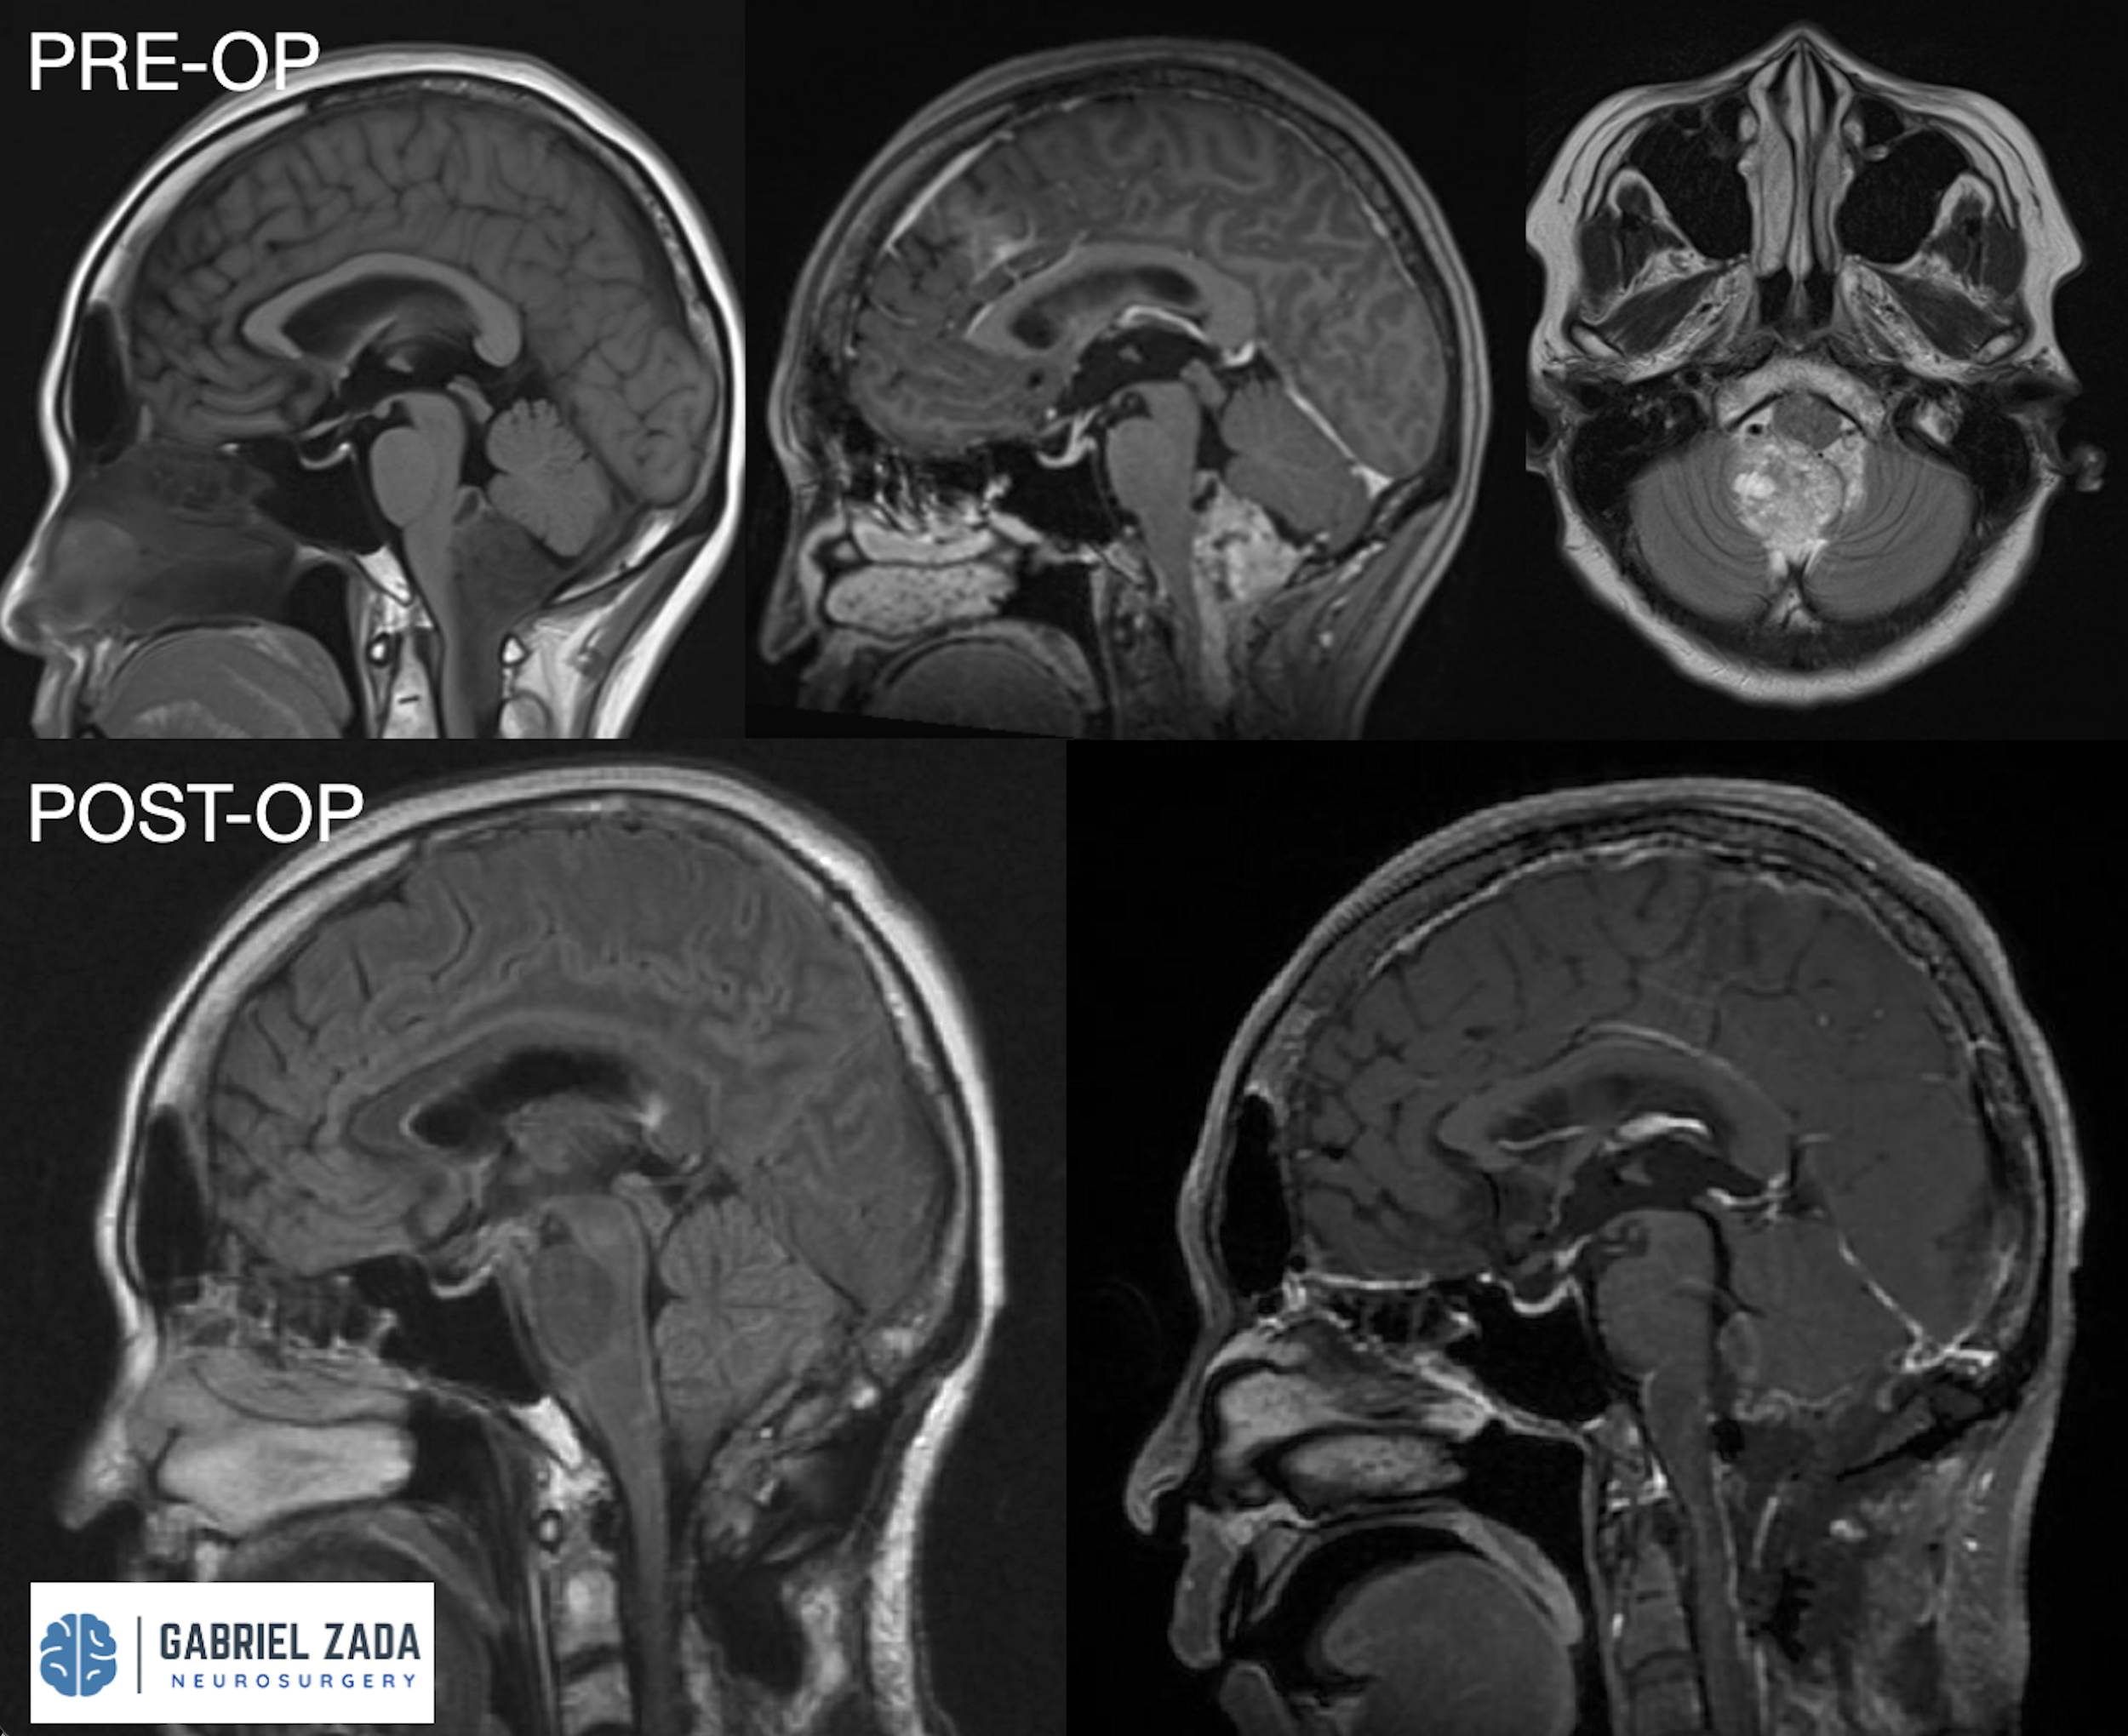

Explore this comprehensive gallery featuring pre‑ and post‑operative imaging of patients with skull‑base tumors treated by Gabriel Zada, MD, MS, FAANS, FACS. These cases highlight Dr. Zada’s expertise in advanced neurosurgical techniques and outcomes.

*Representative cases shown for educational purposes. All images de-identified. Individual results vary.